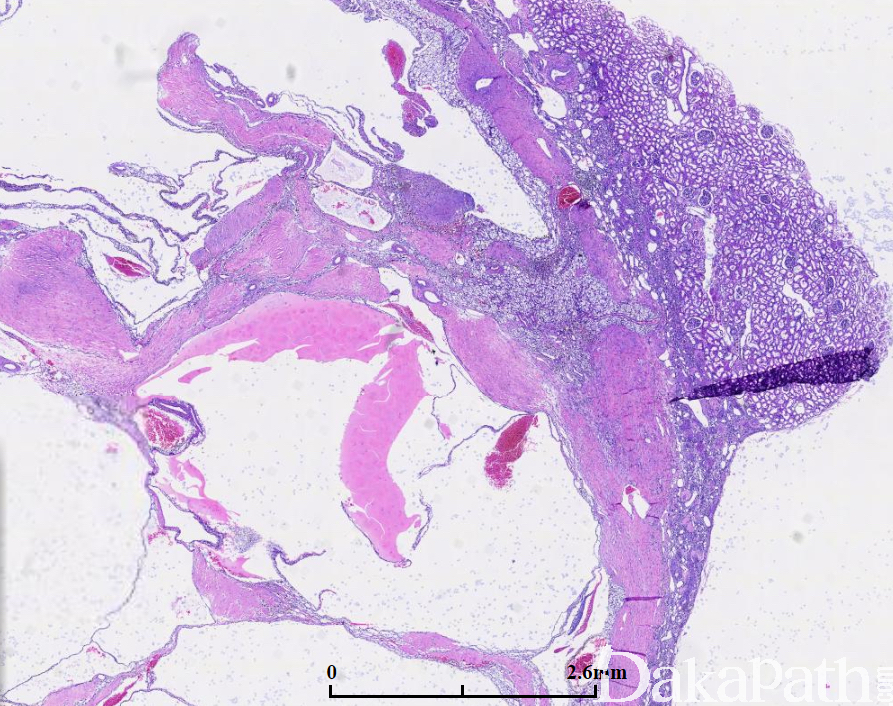

完全由囊腔构成的肿瘤,囊腔间隔内有小灶状透明细胞,形态上与低级别透明细胞肾细胞癌不能区别,无复发及转移报道。

占肾细胞癌不足 1%,主要发生于中年(平均年龄约 52 岁),绝大多数无症状为偶然检查发现;影像学上常表现为 Bosniak II 级或 III 级;

平均直径 4-7cm,大体检查肿瘤有包膜,完全由大小不等的囊腔组成,囊内充以浆液性或血性液体,囊间隔窄偶见钙化,肉眼可见的实性囊壁结节应排除该肿瘤的诊断;

肿瘤性坏死、血管侵犯及肉瘤样转化应排除该肿瘤的诊断。